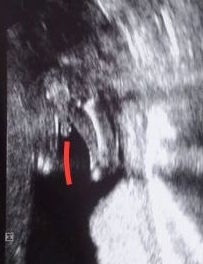

К сожалению на таком сроке не делали узи. Есть фото немного более позднего периода. Если память не подводит была 20-21 неделя. Зато сказали 100 % мальчик. А выглядит это так: